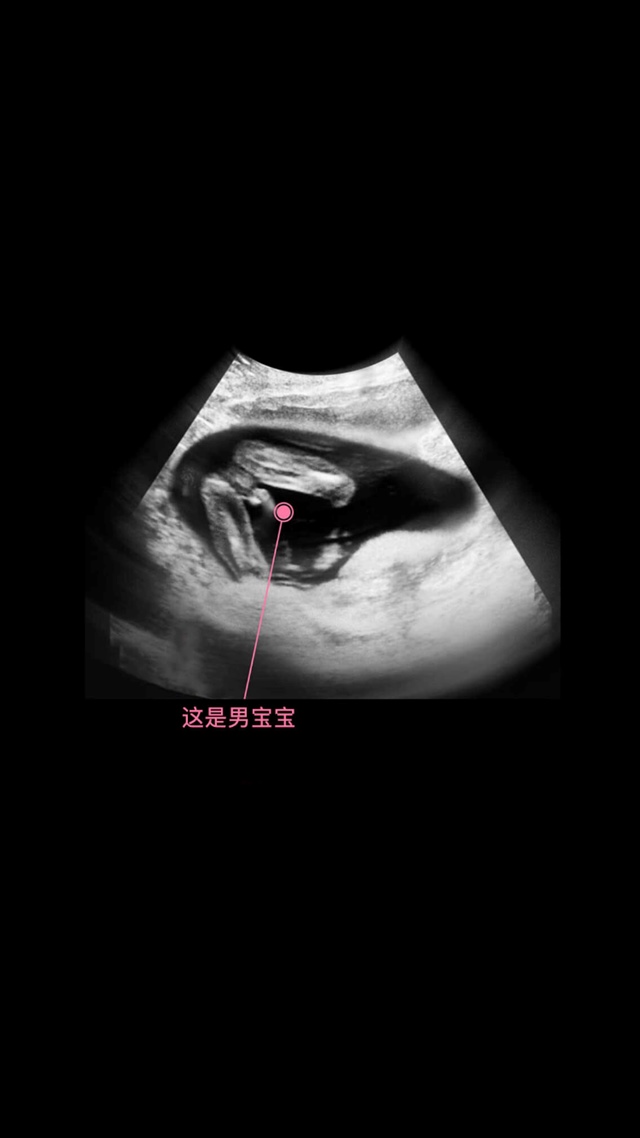

👑Jdan[帖主]:这两个图就是我在美柚上看过的呀,然后才会自己在做四维的时候看出来性别,没说这图是我的娃的

这个是美柚软件里有每周彩超的样子 !15-16周大概能看出来的

👑Jdan[帖主]:我就是在美柚上看到的这两个图,这两图是从美柚那拿过来讲解用的啊